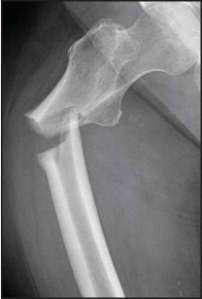

Un estudio anidado de casos y controles realizado con mujeres españolas mayores de 65 años encontró una fuerte asociación entre el uso de bifosfonatos y el aumento del riesgo de fractura femoral atípica. Estos resultados añaden nuevas pruebas a las publicadas en los últimos años en el mismo sentido y hacen obligatoria la prescripción cuidadosa de estos fármacos, evitando su uso en mujeres con bajo riesgo de fractura.

Desde la publicación en 2005 del primer estudio que alertaba sobre los efectos perjudiciales de los bifosfonatos debido a la supresión de la remodelación ósea, se han ido acumulando evidencias, que hemos recogido en varios números (8, 15) de 7SETmanal, sobre el aumento de fracturas atípicas en relación con su uso prolongado.

Este estudio anidado de casos y controles realizado por investigadores de Navarra evaluó la relación entre uso de bifosfonatos y el riesgo de fracturas de fémur en mujeres de 65 años o más de la población española a partir de la base de datos BIFAP (Base de Datos para la Investigación farmacoepidemiológicos en Atención Primaria), que incluye información anónima desde 2001 de> 13,7 millones de persona-años de seguimiento. Una particularidad del estudio es que se ha llevado a cabo en población mediterránea con menor riesgo de fracturas en comparación con los países anglosajones y del norte de Europa.

Los casos se definieron como mujeres de 65 o más años con un primer diagnóstico de fractura subtrocantèrica o diafisaria registrado entre el 1 de enero de 2005 y el 31 de diciembre de 2008, con un seguimiento de al menos 1 año en labase BIFAP antes de la fecha del ingreso (fecha índice). Se excluyeron mujeres con antecedente de cáncer, enfermedad de Paget, fractura de cadera previa o cualquier fractura resultado de traumatismo o accidente de tráfico. Por cada caso se seleccionaron 5 controles sin historia de fractura de cadera en el momento de la fecha índice, emparejados por edad y por el mismo año de registro en la base BIFAP.

El análisis incluyó 44 casos y 220 controles emparejados (media de edad de 82 años). El uso de bifosfonatos en algún momento fue más frecuente en los casos que en los controles (29,6% versus 10,5%) con una odds ratio [OR] de la fractura de fémur atípica de 4,30 (intervalo de confianza [IC] 1,55 hasta 11,9) a favor de las mujeres que habían tomado bifosfonatos frente las que no habían tomado nunca. El riesgo aumentó con el uso prolongado, con una OR de 9,46 (IC 2,17 a 41,3) al comparar el uso de bifosfonatos durante más de 3 años con el no uso.

Los bifosfonatos reducen el remodelado óseo, inhibiendo la resorción a través de la apoptosis de osteoclastos, pero también la formación para que los osteoblastos que la producen son activados por los mismos osteoclastos. Los bifosfonatos también debilitan la estructura de colágeno y producen la acumulación de lesiones microscópicas de la estructura ósea que no pueden ser reparadas por la inhibición concomitante de la formación de hueso. Además hay un patrón radiológico que se repite en las fracturas relacionadas con bifosfonatos y se ha definido una localización típica de estas en las regiones del fémur donde hay una carga máxima de tensión.

Así pues, hay razón biológica, radiológica y mecánica para explicar el aumento de fracturas atípicas con el uso de bifosfonatos.

Una de las principales limitaciones es el número pequeño de casos, que impide hacer análisis de subgrupos de fármacos y la no disponibilidad de las imágenes radiológicas de las fracturas, aunque se disponía de los informes detallados de los procedimientos quirúrgicos para tratarlas. Un diseño de cohortes permitiría obtener mejor evidencia.

La fuerte asociación entre el uso de bifosfonatos y el aumento del riesgo de fracturas atípicas en mujeres españolas de más de 65 años y bajo riesgo de fractura encontrada en este estudio, se añade a la evidencia acumulada con otros estudios realizados con poblaciones con más riesgo y pone de relieve que hay que ser muy cuidadosos a la hora de indicar bifosfonatos. Especialmente en nuestro medio podría ser peor el remedio que la enfermedad.

Bisfosfonatos y riesgo de fractura atípica de fémur

Los bisfosfonatos se asocian con un incremento del riesgo de aparición de fracturas atípicas femorales, por lo que se recomienda a los profesionales sanitarios lo siguiente:

- examinar ambas extremidades en pacientes tratados con bisfosfonatos que puedan presentar una fractura atípica femoral, ya que frecuentemente son bilaterales

- valorar la suspensión del tratamiento con el bisfosfonato en base a la situación clínica del paciente, en caso de que se sospeche la aparición de una fractura atípica

- reevaluar periódicamente la necesidad de continuar el tratamiento con bisfosfonatos en cada paciente, particularmente después de 5 años de tratamiento

Los bisfosfonatos son la pieza central de la farmacoterapia en la osteoporosis. Sin embargo, han surgido preocupaciones de que su uso a largo plazo puede aumentar relativamente algunos de los tipos raros de fractura debido a la supresión de la remodelación ósea. Estos investigadores de Canadá y Arabia examinaron si la terapia con bifosfonatos durante más de cinco años se asocia con un mayor riesgo de fractura de tipos diferentes. Se realizó una base poblacional, estudio de casos y controles anidado en una cohorte de mujeres de 68 años de edad y mayores que se iniciaron con bisfosfonatos orales. Los casos con una fractura de la diáfisis femoral o subtrocantéreas fueron emparejados con un máximo de 5 controles.

«Los investigadores informaron: «Se identificaron 716 mujeres que sufrieron fractura de la diáfisis femoral o subtrocantéreas después de la iniciación de la terapia con bifosfonatos y 9.723 mujeres que sufrieron una fractura osteoporótica típica de la región intertrocantérea o del cuello del fémur en comparación con el uso transitorio de bifosfonatos, el tratamiento durante 5 años o más se asoció con un mayor riesgo de fractura de la diáfisis femoral o subtrocantéreas (odds ratio ajustado, 2,74). Reducción del riesgo de fracturas osteoporóticas típicas producido entre las mujeres con más de 5 años de tratamiento con bisfosfonatos (odds ratio ajustado, 0,76). Entre las 52.595 mujeres con al menos 5 años de tratamiento con bisfosfonatos, una fractura de la diáfisis femoral o subtrocantéreas ocurrió en 71 (0,13%) durante el año siguiente y 117 (0,22%) después de 2 años. »

Los investigadores concluyeron: «Entre las mujeres mayores, el tratamiento con un bifosfonato de más de 5 años se asoció con un mayor riesgo de eje subtrocantéreas o fracturas femorales. Sin embargo, el riesgo absoluto de estas fracturas es baja.